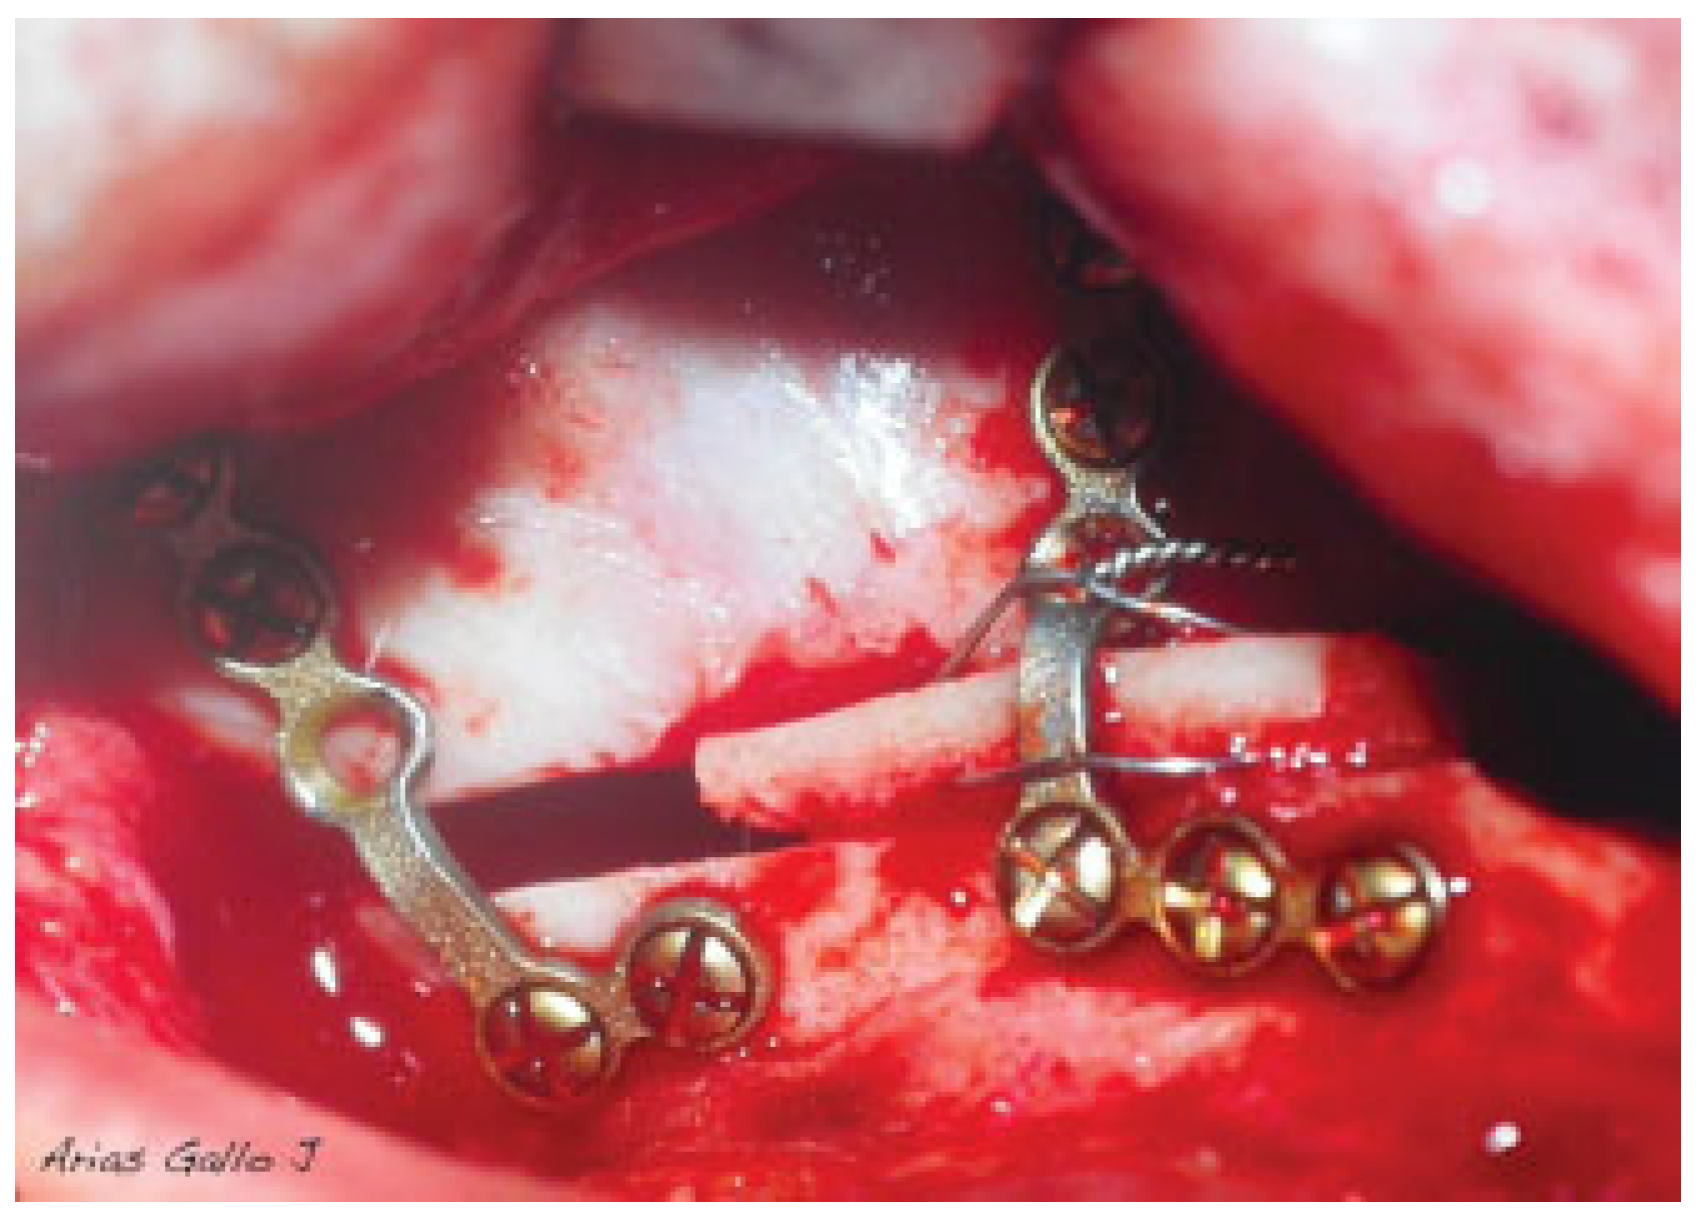

Figure 1.

Fixation of the bone blocks with a wire that goes beyond the graft and anchors the plates.